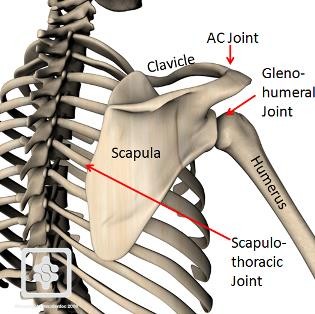

Shoulder Anatomy

The clavicle is located between:

- The sternum (breastbone)

- The scapula (shoulder blade)

It acts as a strut that holds the shoulder away from the chest and allows free arm movement.

The clavicle lies above important nerves and blood vessels, which are carefully assessed in cases of fracture.